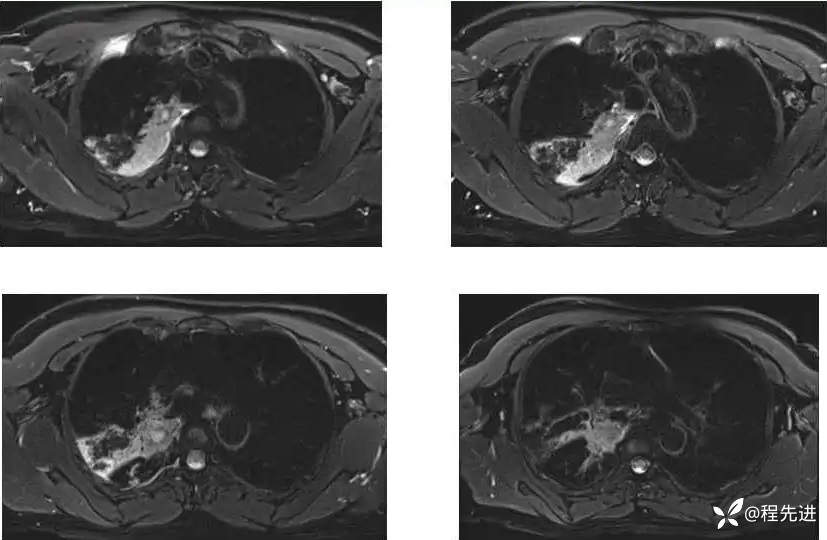

MR平扫+增强:

T2压脂: